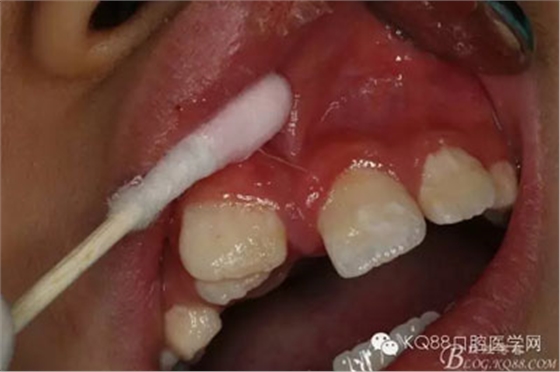

圖4.局部粘膜先涂表麻膏

圖5.唇側(cè)無痛浸潤(rùn)麻醉